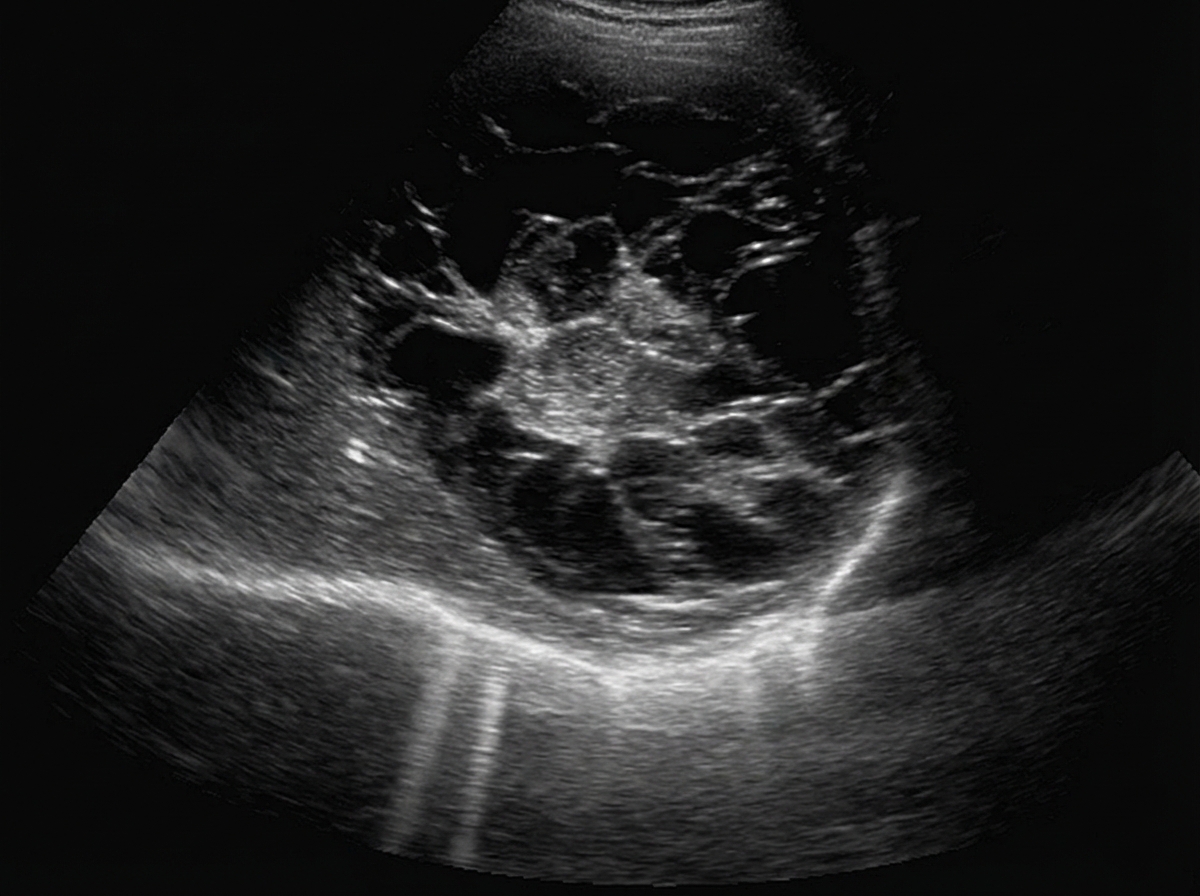

A patient presents with complaints of fever and abdominal distention. He is having history of bloody diarrhea off and on for previous 6 months. X-ray abdomen is shown below. What is the diagnosis?

Explanation: ***Toxic megacolon*** - The image shows **marked dilation of the colon** with loss of haustral markings, consistent with megacolon. - The clinical picture of fever, abdominal distention, and bloody diarrhea in a patient with a history of inflammatory bowel disease (implied by chronic bloody diarrhea) strongly suggests **toxic megacolon**. - Toxic megacolon is a life-threatening complication of IBD requiring urgent management. *Pneumatosis intestinalis* - This condition involves **gas within the wall of the bowel**, which would appear as characteristic lucencies outlining the bowel wall on X-ray. - While it can be seen in severe bowel ischemia, it is not the primary finding of diffuse colonic dilation seen here. *Volvulus* - Volvulus is a **twisting of a loop of intestine** around its mesentery, leading to obstruction and ischemia. - While it can cause colonic dilation, the dilation is typically localized to the twisted segment (e.g., a "coffee bean" sign in sigmoid volvulus) rather than the diffuse involvement seen here. *Intestinal perforation* - Intestinal perforation is characterized by the presence of **free air under the diaphragm** (pneumoperitoneum) on an upright chest X-ray or lateral decubitus abdominal film. - While a severely dilated and inflamed colon can perforate, there is no clear evidence of free air outside the bowel wall in this X-ray. *Paralytic ileus* - Paralytic ileus causes **generalized bowel dilation** and can present with abdominal distention. - However, it typically involves both small and large bowel, lacks the **loss of haustral markings** specific to toxic megacolon, and does not typically present with **fever and bloody diarrhea** in the context of chronic inflammatory bowel disease.